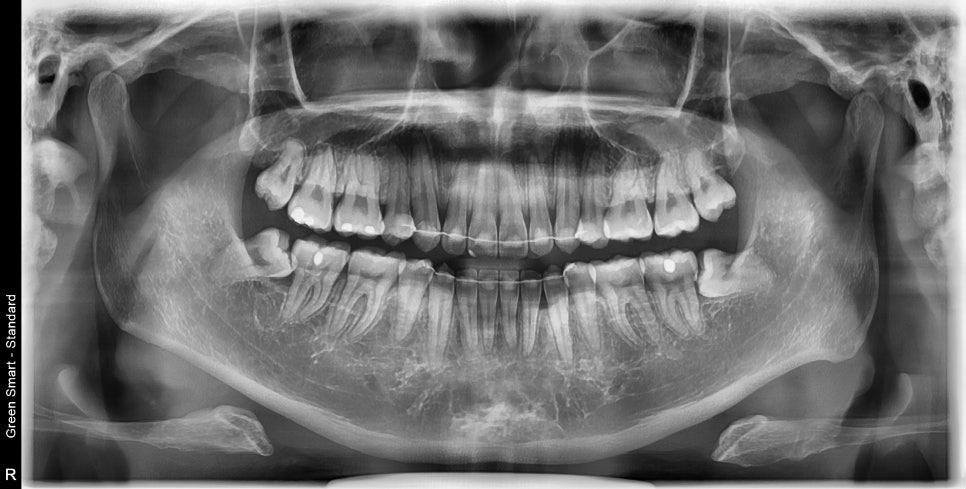

결국 2년이라는 시간이 지나고 교정이 마무리 되었습니다. (장치 제작기간 2달 포함, 처음 한달 + 재제작시 한달)

치아의 배열이 확인됩니다.

비베라를 이용한 유지를 하기로 해서 제작을 기다리고 있습니다.